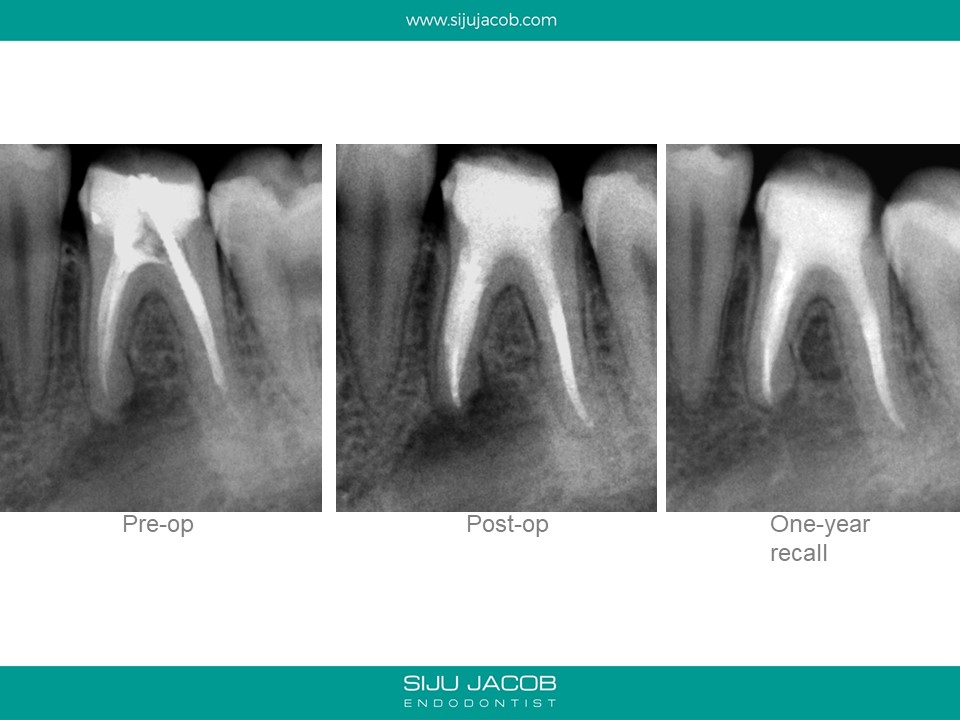

This is a case from 12 years ago. I re-treated all the canals including the distal which had a metal post. At, the one-year recall, the mesial root seems to have healed well. Today, I would probably have left the distal root alone and not over-enlarged those mesial canals.